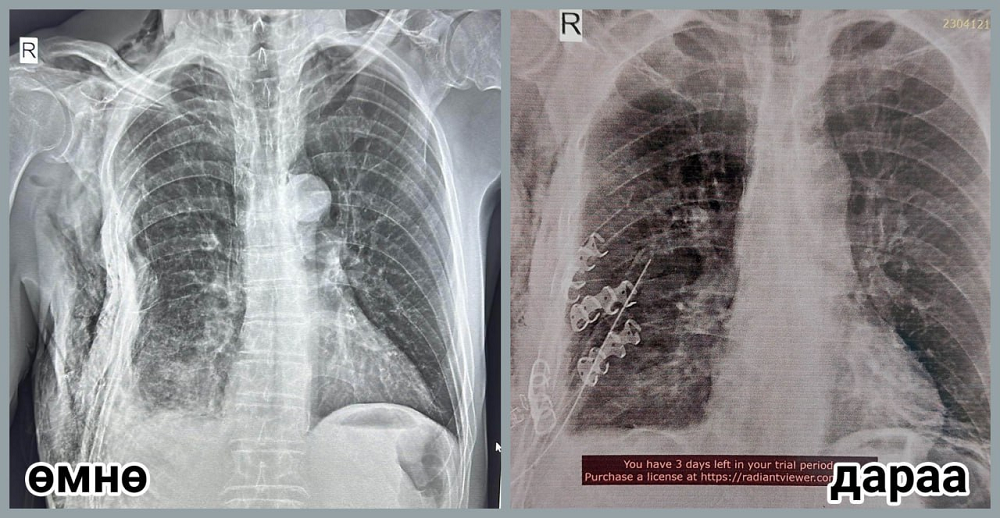

Гэмтэл согог судлалын үндэсний төвийн Хавсарсан гэмтлийн тасгийн эрхлэгч, их эмч П.Баярсайханаар ахлуулсан баг энэ сарын 9-нд алсын дуудлагаар Булган аймагт очиж мориноос унаж цээжний хөндийн хүнд бэртэл авсан өвчтөнд мэс заслын яаралтай тусламж үзүүллээ.

П.Баярсайхан эмчийн багт ГССҮТ-ийн мэс заслын их эмч С.Мөнхлхагва, резидэнт эмч Д.Мөнхзул, Мэс заслын нэгдсэн тасгийн сувилагч Б.Алтанцоож, жолооч С.Бүрэнтөгс нар багтсан бөгөөд тэд Булган аймгийн Нэгдсэн эмнэлгийн гэмтлийн их эмч Д.Алтангэрэл, мэс заслын их эмч Н.Энхжаргал, мэдээгүйжүүлгийн их эмч Т.Батдорж, мэс заслын сувилагч С.Ганчимэг, мэдээгүйжүүлгийн сувилагч Х.Хандсүрэн нартай хамтран өвчтөний хавирганы тогтворгүй хугарлыг бэхлэх мэс заслыг амжилттай хийсэн байна. Өвчтөний биеийн байдал сайжирч, тогтворжсон бөгөөд өдгөө аймгийнхаа Нэгдсэн эмнэлэгт мэс заслын дараах эмчилгээ хийлгэж байгаа юм.

ГССҮТ-ийн мэс заслын баг сүүлийн таван жилийн хугацаанд цээжний хөндийн битүү гэмтэл буюу хавирганы тогтворгүй хугарлыг бэхлэх мэс заслыг орон нутагт нутагшуулах замаар нийт 21 аймагт ажиллаж байна.